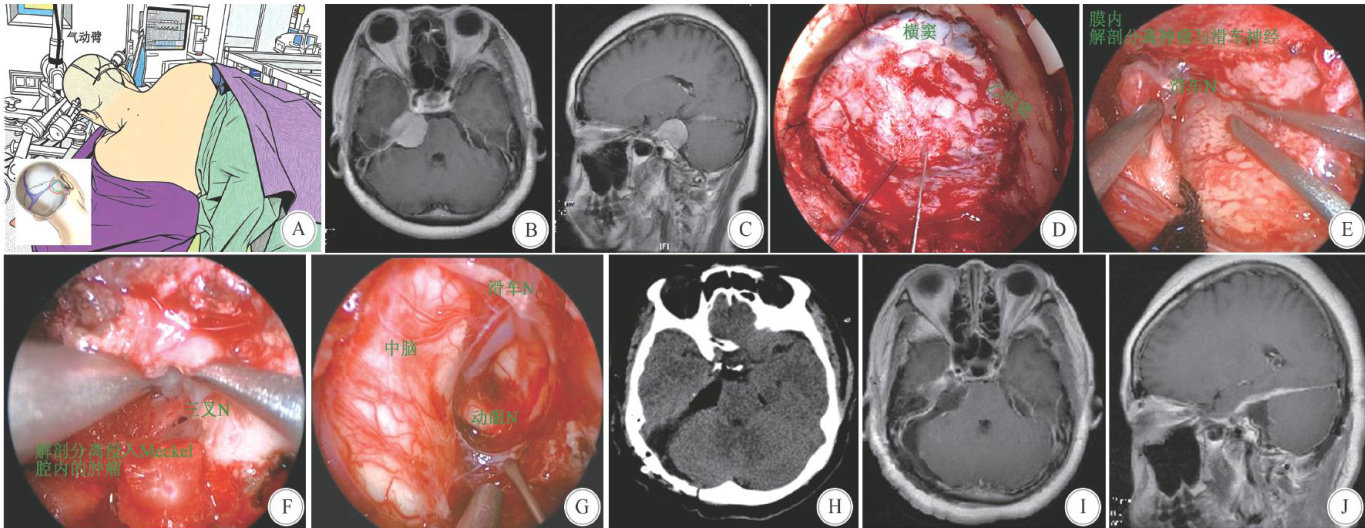

神经内镜下经远外侧幕下小脑上入路切除岩斜区肿瘤的临床实践与技术解析

Abstract:ObjectiveTo explore the technical key points,clinical eficacy and advantage mechanism of resectionofpetroclival region tumorsvianeuroendoscopicfar-lateral supracerebellar infratentorialapproach(EFLSCITA),soas toprovidereference forclinical practice.MethodsTheclinical dataof7patients with petroclival regiontumors whounderwent surgicalresectionvia EFL-SCITAintheAfiliated Hospitalof XuzhouMedical University from January2O2O to May2O23wereretrospectivelyanalyzed.Theintraoperative technical keypoints and postoperativeeffcacy were analyzed.ResultsAmong the7patients,5 had total tumor resection and2 had subtotal resection.Postoperative pathologyconfirmed2cholesteatomasand5meningiomas.Noneof the7patientssffred from nerve injury,and1 meningioma patient developed cerebellar contusion and edema postoperatively.No deaths occurred.Followed up for 1~2 years,all7 patients lived normally without recurrence.ConclusionsResection of petroclival region tumors via EFL-SCITA has the advantages of minimal trauma,clear vision,and less complications, especiallyinprotecting nervefunctionand improving thetotal tumorresectionrate,whichisworthyofclinical promotion and application.

KeyWords:petroclival region tumor;neuroendoscopy;far-lateral supracerebellar infratentorial approach

岩斜区位于颅底中央,涵盖鞍背至斜坡上2/3区域,是脑膜瘤、神经鞘瘤、表皮样囊肿等病变的好发部位[1-4]。(剩余9363字)